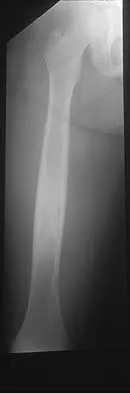

A 10-year-old boy with a history of retinoblastoma now reports right knee pain. AP and lateral radiographs are shown in Figures 3a and 3b. What is the most likely diagnosis?

Explanation

The radiographs show a bone-producing lesion in the femoral diaphysis. The radiographic appearance of small round cell tumors is more permeative with an elevated periosteum and no matrix production. The appearance of this lesion is most consistent with osteosarcoma. Patients who carry the Rb gene are predisposed to osteosarcoma. However, Ewing's sarcoma, primitive neuroectodermal tumor, and osteomyelitis can all occur in this location. Unni KK: Dahlin's Bone Tumors: General Aspects and Data on 11,087 Cases, ed 5. Philadelphia, PA, Lippincott-Raven, 1996, pp 143-160.